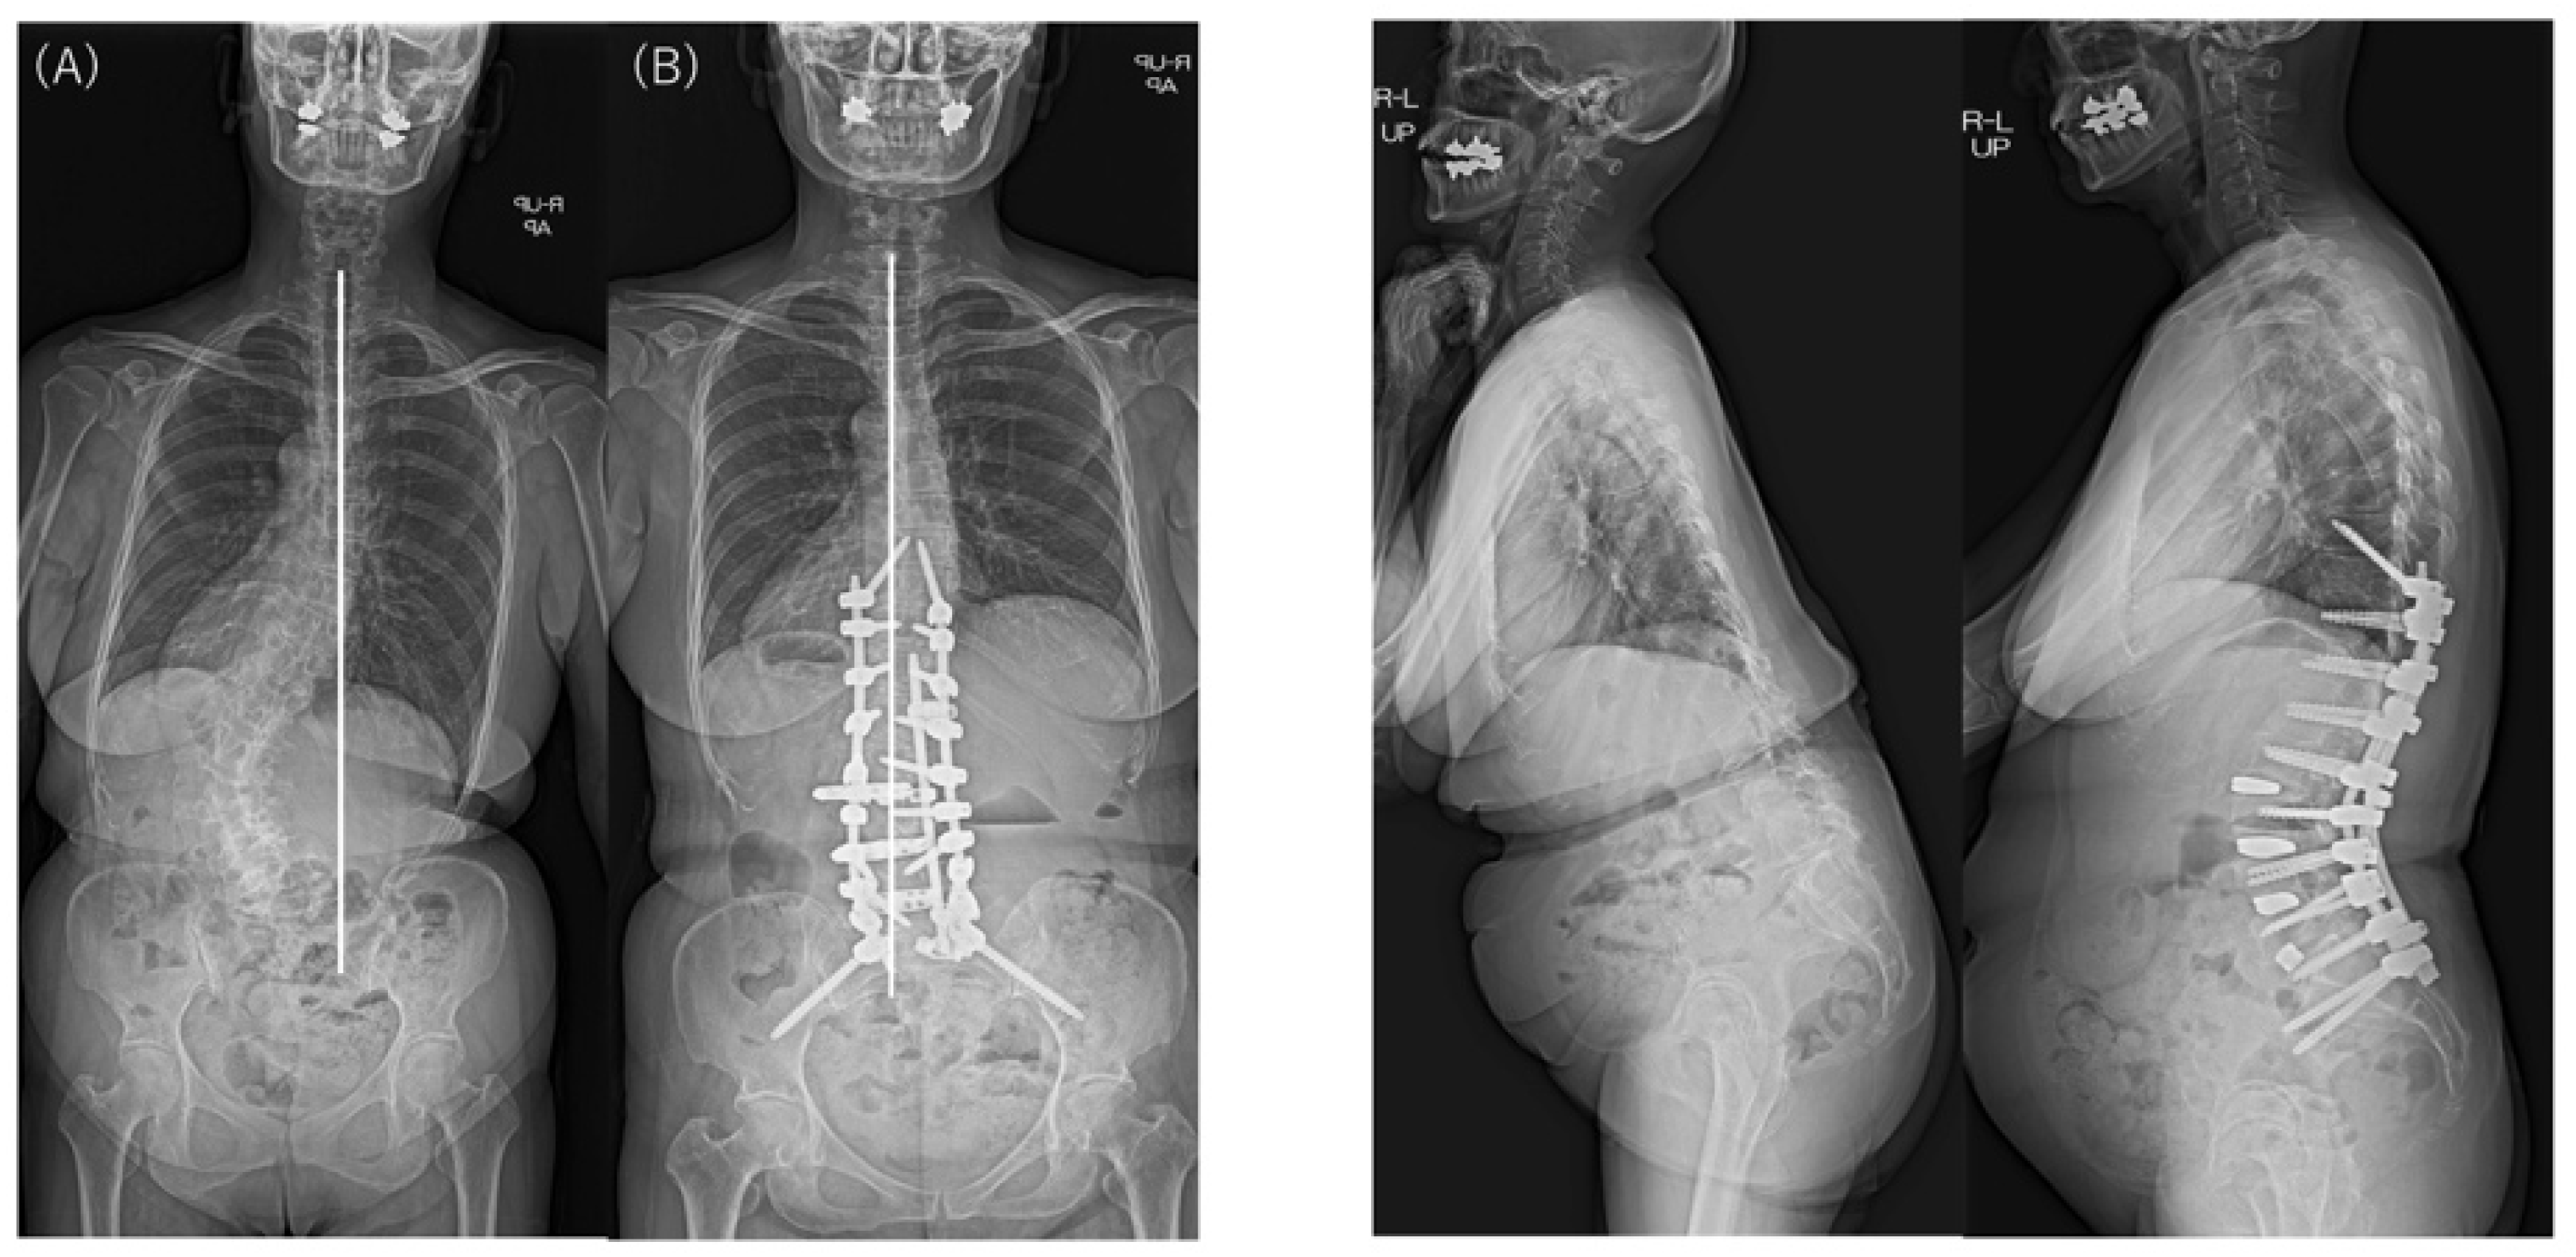

| Major Cobb angle (°) | Preop | 50.0 (11.4) | 44.3 (11.4) | 48.8 (11.5) | 0.286 |

| Last | 12.9 (11.9) | 14.2 (8.0) | 13.2 (11.1) | 0.810 | |

| p † | <0.001 * | 0.002 * | <0.001 * | ||

| │CBD│ (mm) | Preop | 78.4 (51.6) | 46.9 (21.7) | 71.9 (48.5) | 0.159 |

| Last | 22.8 (28.0) | 38.5 (20.4) | 26.0 (27.0) | 0.211 | |

| p † | <0.001 * | 0.506 | <0.001 * | ||

| SVA (mm) | Preop | 168.0 (75.9) | 172.9 (35.1) | 169.0 (69.0) | 0.879 |

| Last | 36.3 (56.3) | 53.3 (39.9) | 36.9 (53.4) | 0.494 | |

| p † | <0.001 * | 0.001 * | <0.001 * | ||